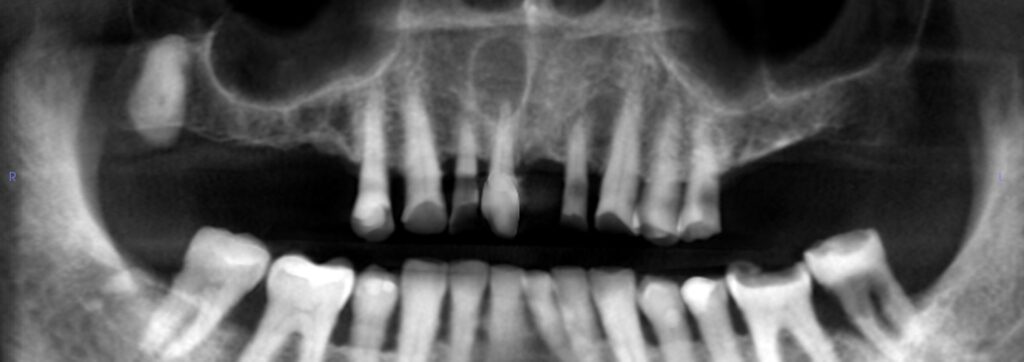

7-year-old boy with mandibular radiolucency